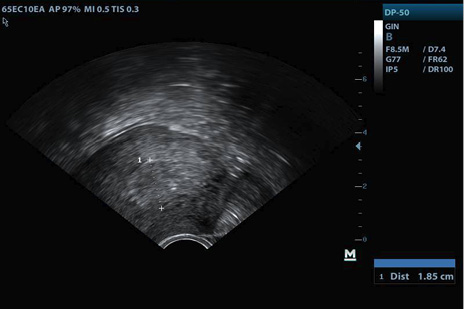

La evolución en controles subsiguientes evidenció persistencia del sangrado genital y dolor pélvico, sin signos de infección, endometrio ecográficamente mixto sin disminución de grosor (Figuras 2-3), y niveles de GCH en descenso lento, por lo que a los 28 días después de la expulsión se decidió prueba terapéutica con misoprostol dosis única vaginal, sin éxito.

Figura 2. Corte longitudinal de endometrio primer control ecográfico

Fuente: archivo personal del autor, con autorización de la paciente.

Figura 3. Corte longitudinal de endometrio segundo control ecográfico